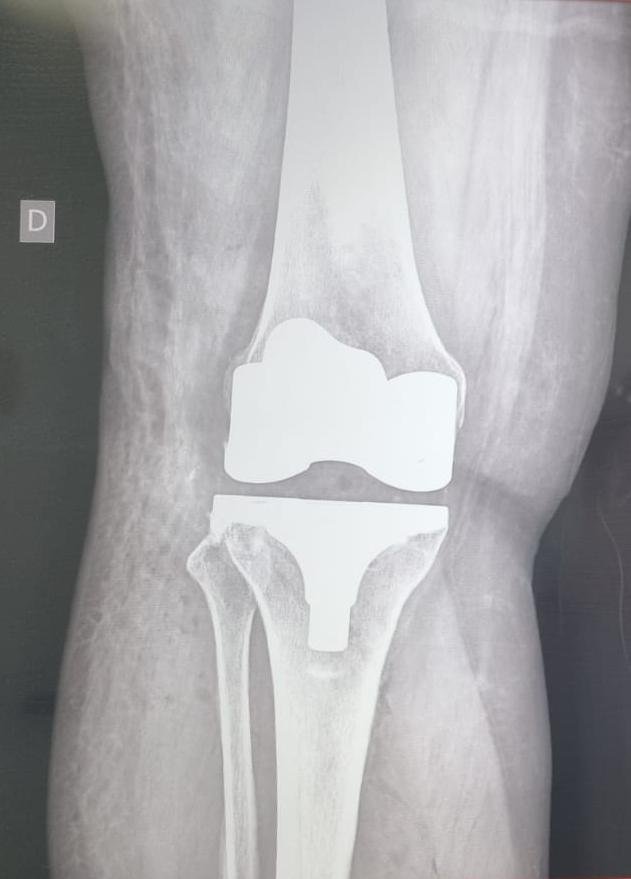

El Dr. José Luis Rodríguez García cuenta con el título de Especialista en Ortopedia y Traumatología.